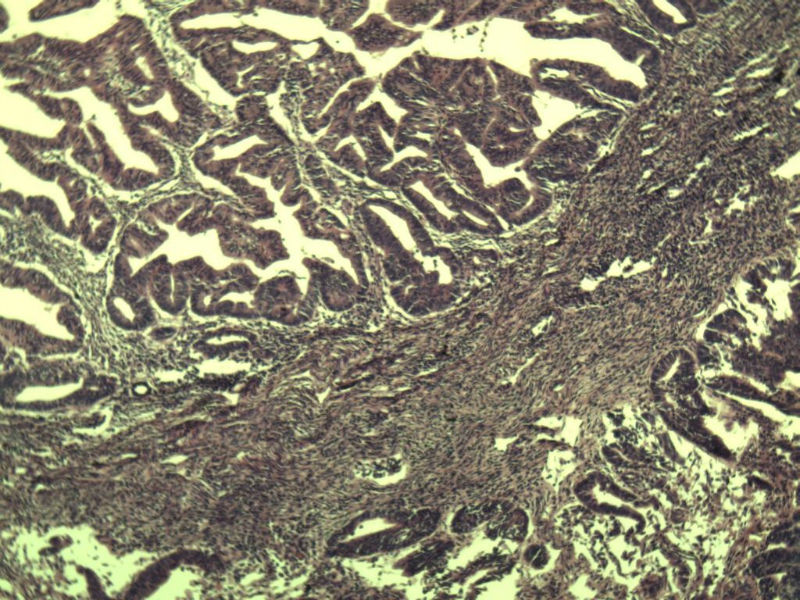

名称:图3

描述:a146.Jpg.jpg